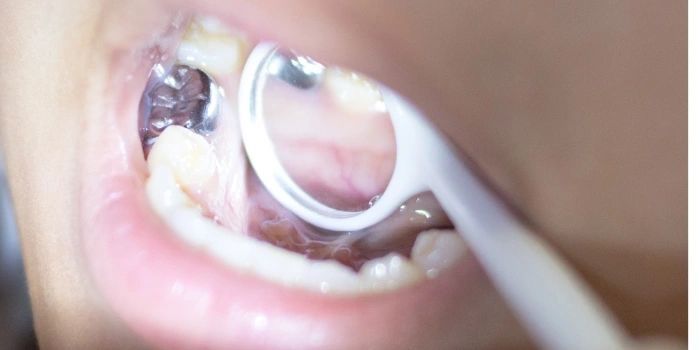

Pulpotomies

When the nerve (pulp) tissue of a baby tooth is first infected (affected), it needs to be treated to prevent further damage, which could result in a dental abscess and loss of the tooth. The ultimate objective of this procedure is to save the tooth so that it will maintain the integrity and function of the dental arch.

Stainless Steel Crowns

A stainless steel crown is an extremely durable silver metal crown that has pre-formed anatomy and can be adapted to the tooth at the edges. Although they do not possess as good esthetics as we would like, stainless steel crowns have both research- and time-proven records of durability, longevity, and biocompatibility. They do not hinder the loss of primary teeth and do not affect the development of permanent teeth.